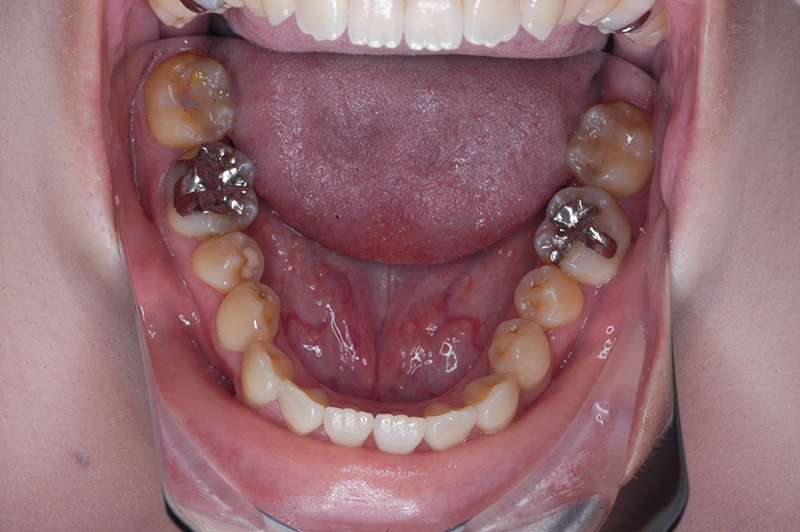

動的治療終了時

FP・IOP

批評・予后 ロウアングルのSkeletal Ⅲ級であり、下顎臼歯は近心傾斜しつつ7遠心部にはアップライトができるスペースがあると判断して、MEAWによる咬合平面の平坦化および可及的な下顎のカウンタークロックワイズローテーションによって改善を行うこととした。治療後には歯列の整直とⅠ級の咬合が得られた。(H30年9月現在で)保定開始4年経過しているが現在も咬合は安定している。